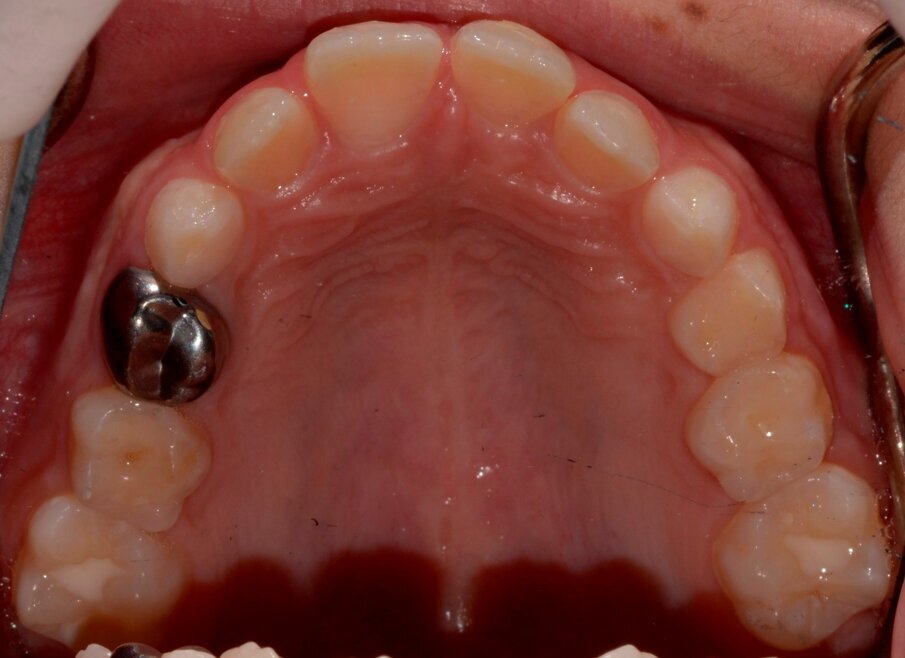

Radiographic examination

Periapical views of the upper maxillary incisors were obtained to rule out any root fractures (See Figures 4 a & b) revealed immature roots of teeth # 12, 11, 22, no root fractures and an inverted supernumerary apical to 11 and an empty socket of 21. There was no need for soft tissue radiographs as no tooth fragments were missing and the tooth was accounted for.

Figure 2: Palatal view of 21 socket. Notice the coagulum filled socket